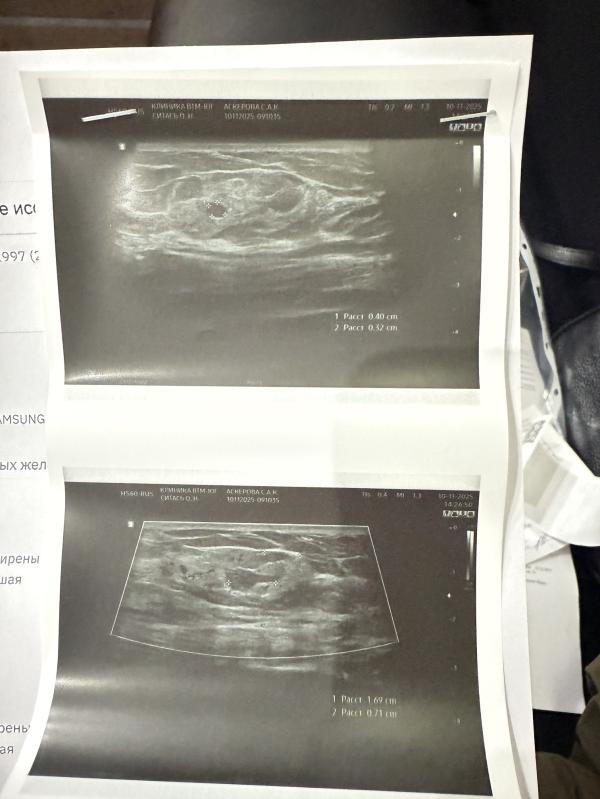

На узи сказали инфильтрат 2см и в нем два лимфатических узла

Категория Bi-rads 2 - доброкачественные изменения. Скорее всего скажут просто наблюдать раз в год.